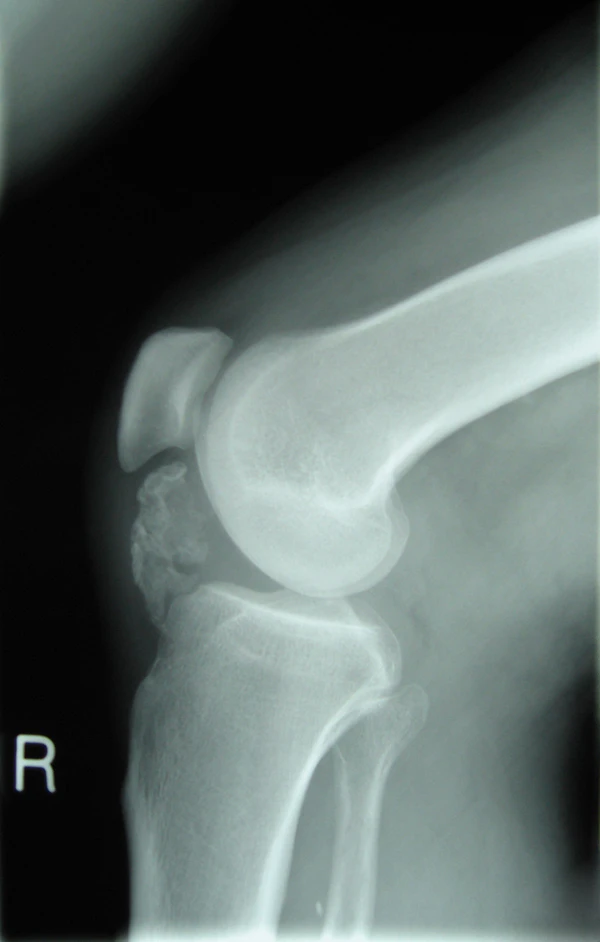

Рентгенография

Остеохондромы представляют собой поверхностные поражения. Они обычно локализуются в метафизе и характеризуются непрерывностью кортикального и медуллярного слоёв, а также наличием хрящевой шапочки. Опухоли могут быть на широком или узком основании. Рентгенологические признаки, указывающие на злокачественную трансформацию, включают увеличение размера, изменение морфологии, периостит или появление нечёткости кортикальных краёв. Поражения плоских костей часто неоднозначны на рентгенограммах и требуют дополнительной визуализации для подтверждения кортикомедуллярной непрерывности[3][7]